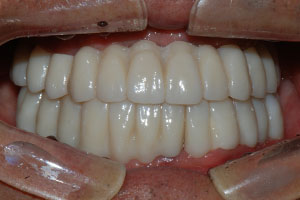

치료증례 전후사진

Before & After